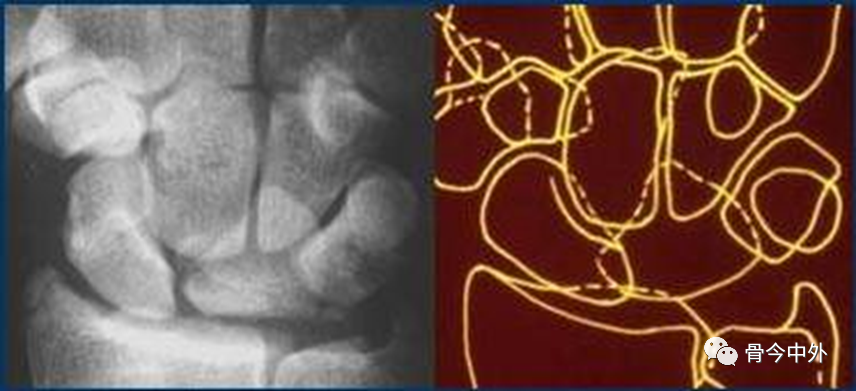

图18

弧线Ⅱ 中断于舟月关节和月骨-三角骨关节(上图)。弧线Ⅰ虽有缺口但仍呈光滑弧线,可认为是完整的。